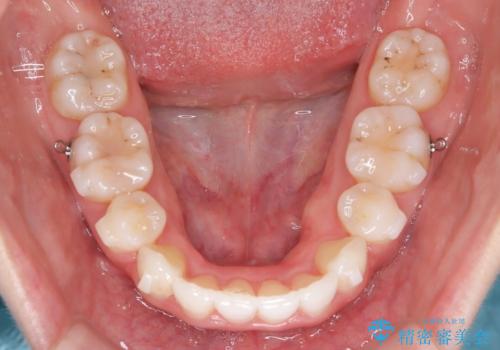

【抜歯インビザ】凸凹を綺麗になおしたい

- 前歯の凸凹を主訴に来院されました。

叢生量が多いため、抜歯が必要となるため、ワイヤー矯正をお勧めしましたが、患者さんの希望によりインビザラインで治療を開始しました。途中でワイヤーリカバリーを必要とせず終了でき患者さんには満足していただけました。